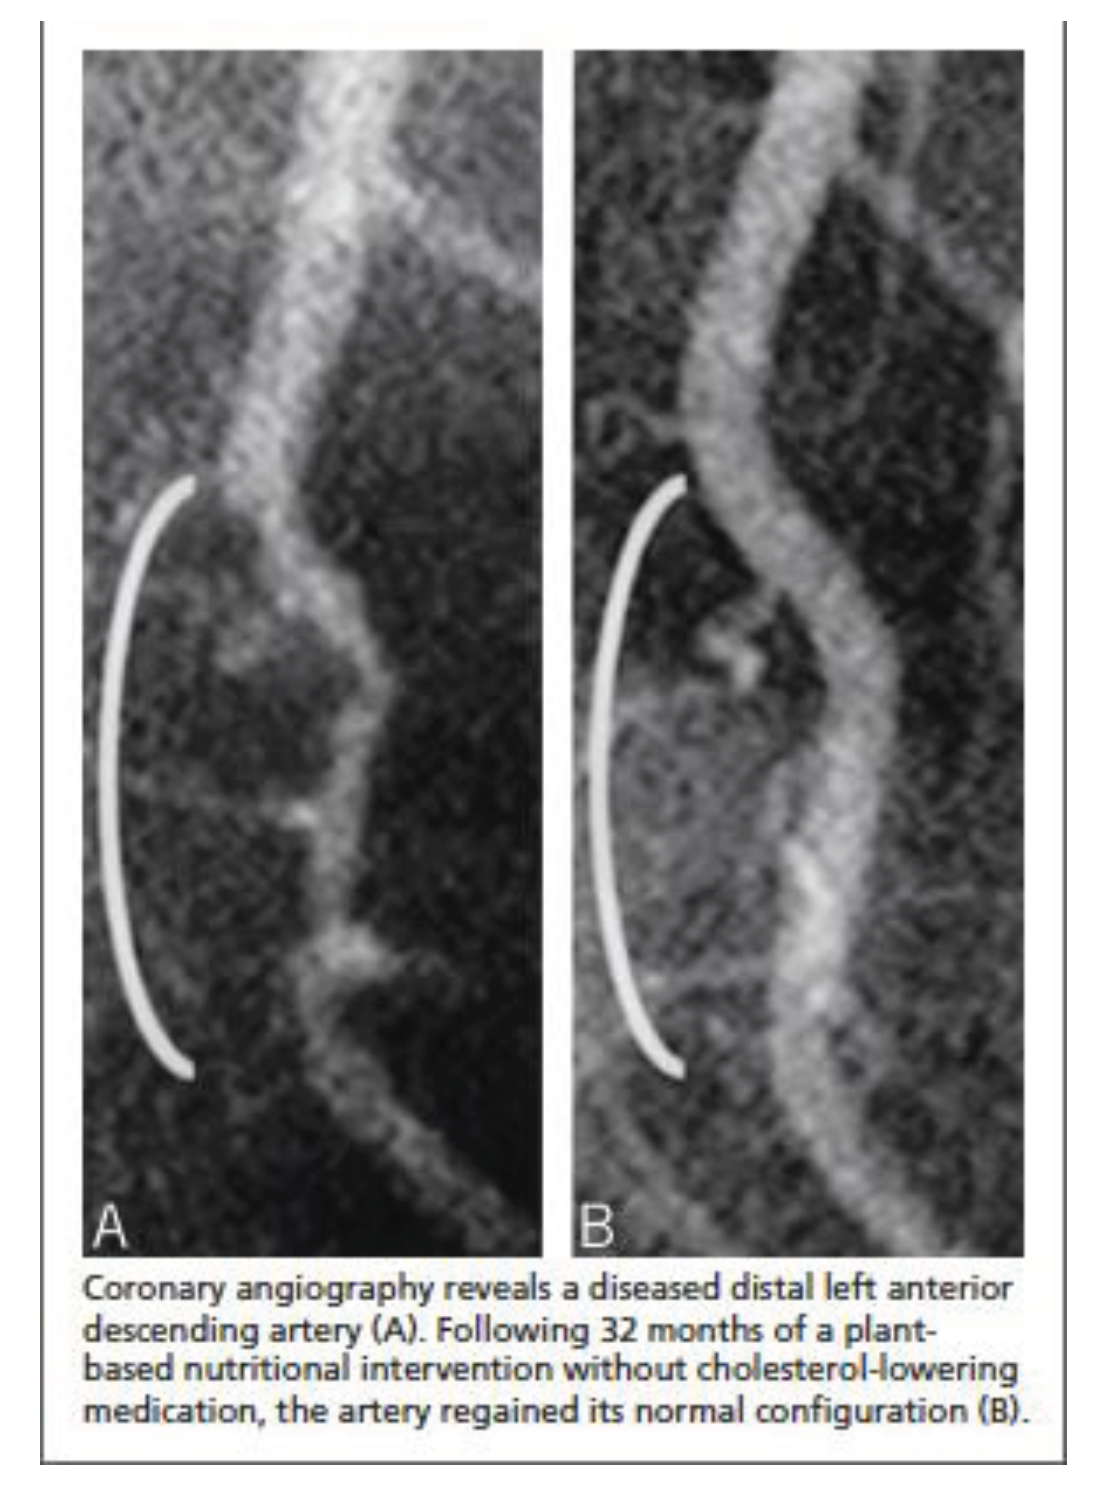

- Esselstyn, C.B., Jr.; Gendy, G; Doyle, J; et al. A way to reverse CAD? J Fam Pract. 2014, 63, 356–364b. [Google Scholar] [PubMed]